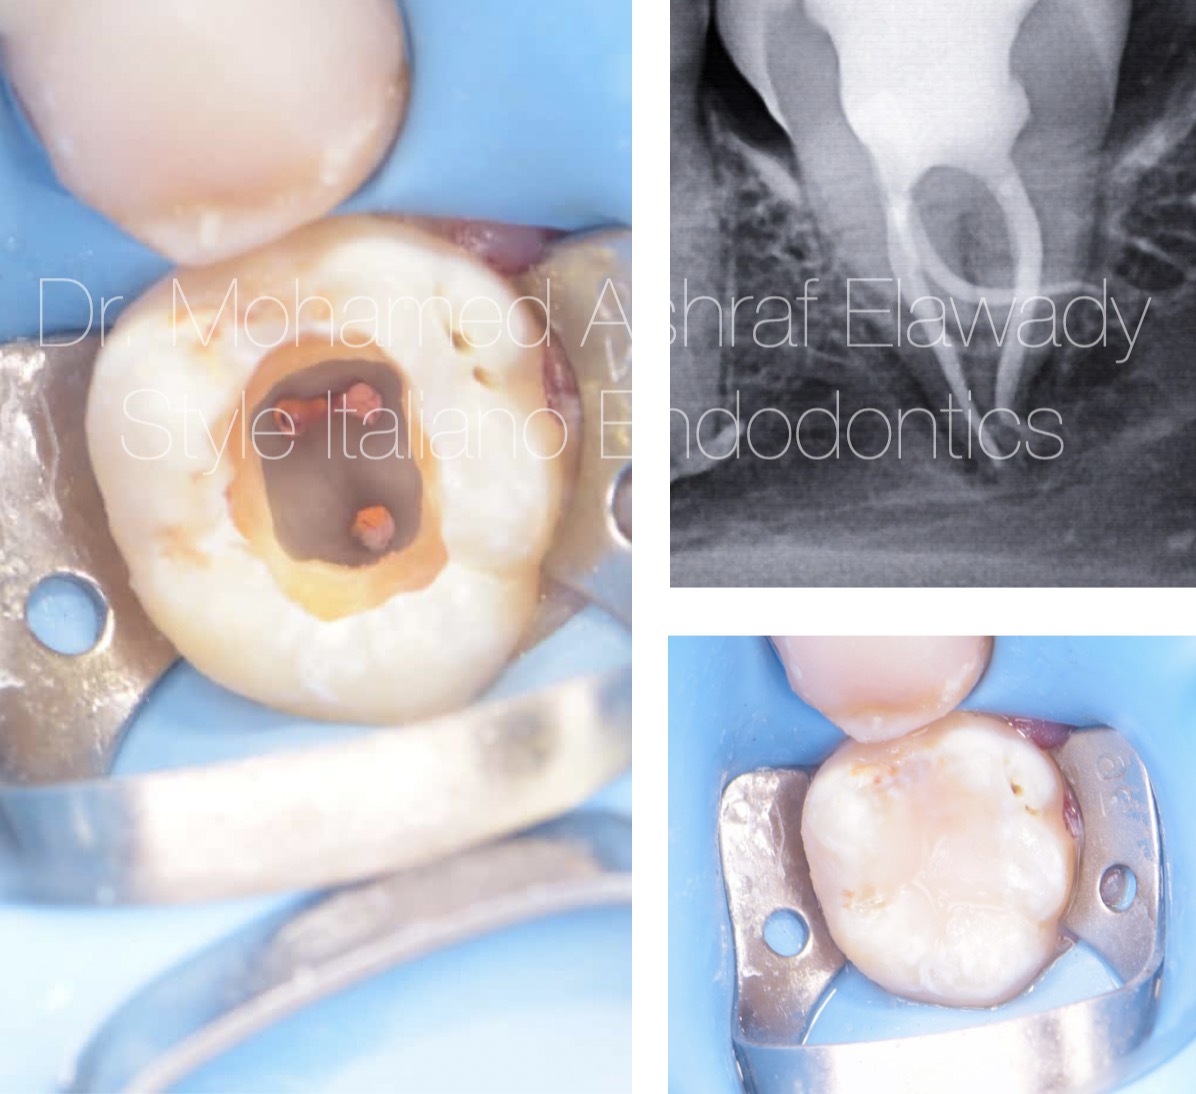

Shaping severely curved canals using rotary files in OTR mode and reciprocating mode combines the benefits of both techniques for optimal control. OTR mode, with its gentle oscillating motion, helps minimize stress on the instrument, reducing the risk of file fracture or canal transportation. It’s ideal for negotiating tight curves, as the oscillation allows the file to glide through the canal with less force. Reciprocating mode, on the other hand, uses back-and-forth motion to effectively remove debris while maintaining flexibility and reduce stresses on the file during shaping .this combination ensures safe, efficient shaping of curved canals, with reduced risk of procedural complications, while enhancing overall canal preparation.

Fig. 5

Obturation with modified cwc and bioceramic sealer.

Fig. 8

Panoramic view of the clinical case

Fig. 9